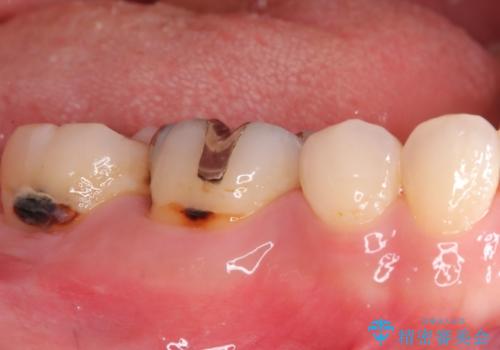

- メタルフリーを主訴に来院されました。

歯牙の破折を防ぐために、セラミッククラウンにて修復しています。